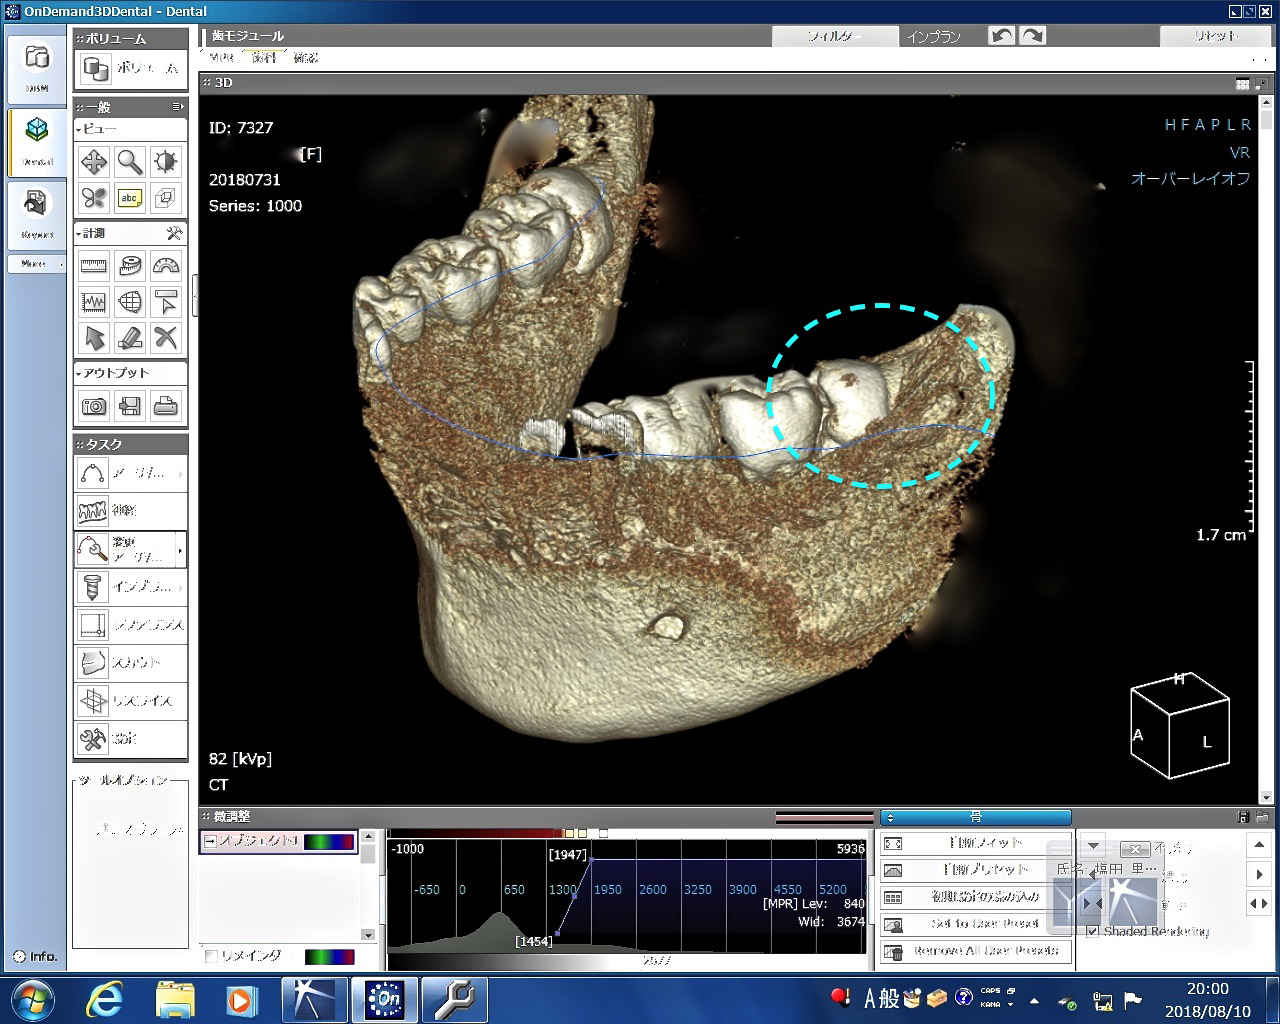

初診時に歯科用CTを撮り、親知らずの生え方をチェックしました。下の奥の親知らずは見事に真横向きで骨の中にがっちり埋まっています。このような難しい生え方をしている親知らずの抜歯は、2回に分けて行った方が身のためであることを説明しました。ただし、帰省までの間に2回も予約スペースがないため、急遽静脈麻酔点滴法(保険適用)を使って、右下の横向きの親知らずの抜歯1本だけをまず行いました。

そして日を改め、帰省する前日の今日、残りの抜歯3本(上2本、下1本=点線)を行いました。